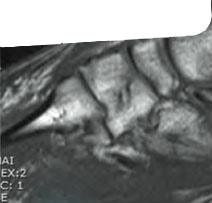

Ressonância Magnética

Músculo Esquelética

- Membros Inferiores - |